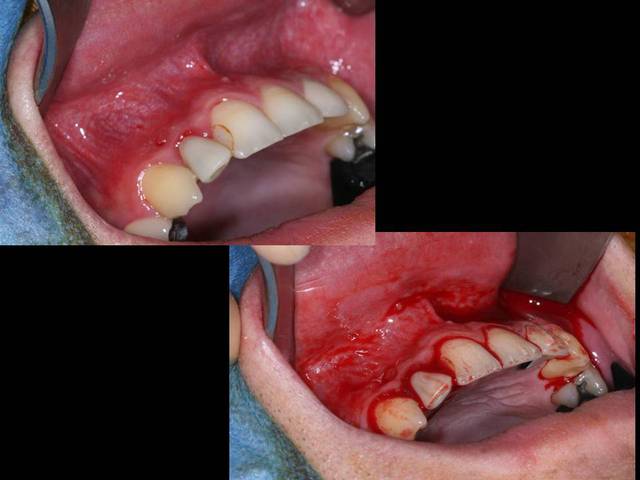

Salut je poste un cas d'un kyste à priori d'origine dentaire avec ROG pour éviter d'avoir un effondrement de la paroi vestibulaire avant pose implantaire.

Comblement au béta TCP pour permettre une résorption totale et un remodelage de la voussure vestibulaire